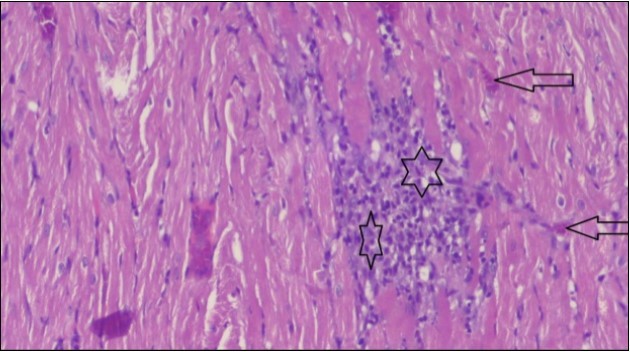

An important organ that is affected directly by the obesity which is the heart: The heart is the main important organ in circulatory system, the heart wall has three basic layers; the tunica intima of the heart is called endocardium, the tunica media of the heart is called the myocardium, the tunica adventitia of the heart the epicardium. The histological examination of the hearts of control rats feeding standard diet showing normal cardiac tissue with elongated, unbranched multinucleated muscle fibers (arrow), (Figure 1). The rats are feeding (HFD) for 2 weeks (obese rats) showing large number of inflammatory cells (star), degeneration muscles fiber ,circle and congested Blood vessels (arrow) (Figure 2). By comparison hearts of rats are treated by fennel after obesity and control rats observed show improved cardiac tissue with less infiltration (star) and well organized elongated muscle fibers with peripheral nuclei (arrow) (Figure 3). While examination of rats heart that treated by ator after obesity appears show less improved cardiac tissue with few inflammatory cells between disorganized muscle fiber (star), (Figure 4). While combined hearts of rats are treated by fennel and ator after obesity and control mice are showing nearly cardiac tissue with well-organized muscles fibers (arrow), (Figure 5).

Figure 1.Photomicrograph of heart section of control rat showing normal cardiac tissue with elongated, un branched multinucleated muscle fibers (arrow), (H&E) (400X).

Figure 2.Photomicrograph of heart section of an obese rat showing large number of inflammatory cells (star), degeneration muscles fiber, circle and congested Blood vessels (arrow), (H&E) (400X).

Figure 3.Photomicrograph of heart section of treated rat with fennel herb showing improved cardiac tissue with less infiltration (star) and well organized elongated muscle fibers with peripheral nuclei (arrow), (H&E) (400X).

These results were confirmed with histological changes of feeding rats heart tissues with high fat diet only, which showed vaculation of tunica media and narrowing in the lumen of aorta sections as well as congestion of cardiac blood vessel and hyalinosis of its wall. This result was confirmed by Szilvassy et al., 78, who indicated that although hyperlipidemia increases oxidative stress in the cardiovascular system, it renders the heart and the vasculature more susceptible to stress. Ouwens et al. 79 identified that development of hyper-cholestremia, which is one of the risk factors for cardio vascular diseases is associated with increased blood levels of TC, LDL-C and VLDL-C as well as lowered levels of HDL in rats fed on high fat-diet. This result was confirmed by histological study, which revealed apparent normal histological structure of heart in all treated rats with fennel seeds. Epidemiologic studies have shown an inverse correlation between HDL-C level and the risk of cardiovascular disease. Increasing the HDL cholesterol level by 1mg may reduce the risk of cardiovascular disease by 2 to 3 percent 80. The present data agreed with Fatiha et al. 81, who reported that hyper-lipidemic rats treated with fennel extract had significant decrease in plasma levels of TL, TG, TC, LDL-C and VLDL, and significant increase in HDL-C level. The current study demonstrates that the alteration induced by high fat diet causing changes in blood parameters. These changes are exhibited through a decrease in RBCs, Ht, Hb and platelet and these changes could be due to oxidative stress, which lead to lipid peroxidation in RBCs membranes, auto oxidation of hemoglobin. As regards the total WBCs, lymphocytes and monocytes showed a marked decrease. While a distinct increase in the percentage of neutrophils and esinophils. The present, demonstrates that rats treated with (fennel), (ator) and (fennel with ator) exposure provided significant protection to the altered haematological variables. The effect of the treatment with fennel and ator is more effective than fennel only or ator only. The current study showed that the serum levels of the total protein and albumin in the obese group were significantly higher than those of the control group. The administration of (fennel) revealed significant decrease in the serum levels of the albumin and total protein as compared to the obesity group, although the serum levels of the albumin and total protein of the Ator group less than the obesity group. Otherwise, the levels of the total protein and albumin in fennel and Ator group were near to the similar value of the control group. The finding of this study indicates that the concentration of Malondialdehyde (MDA) and Myeloperoxidase (MPO) in liver homogenates of the fennel and ator group significant decrease than group (3) and group (4) and obesity group. There is a growing awareness that obesity is a prime risk factor for the development of dyslipidemia profile and that oxidative stress may play a role in various adverse effects of obesity.